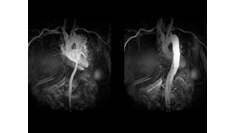

3D Heart

Visualize the anatomical structures and vascularity of the heart with a bright blood, 3D sequence.

Read More

Visualize the anatomical structures and vascularity of the heart with a bright blood, 3D sequence. Read More

SIGNA Works CV Imaging & Analysis Tools

A free breathing, cardiac MR to assess cardiac morphology,function, flow, tissue viability and coronary anatomy without ionizing radiation.  Read More

A non invasive cardiac MR to assess cardiac morphology, function, flow,tissue viability and coronary anatomy without ionizing radiation. Read More

SIGNA™ Works CV Imaging & Analysis Tools

A non invasive cardiac MR to assess cardiac morphology, function, flow, tissue viability and coronary anatomy without ionizing radiation.Read More

A non invasive cardiac MR to assess card ac morphology, function, flow,tissue viability and coronary anatomy without ionizing radiation. Read More